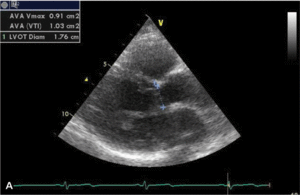

Rycina. Pomiar efektywnego pola ujścia protezy zastawkowej u chorej z wszczepioną sztuczną zastawką aortalną St Jude Medical 21A.

Ocenę funkcji wszczepionej zastawki umożliwia echokardiografia (ryc. 1). Ocena protezy zastawkowej wszczepionej w pozycję aortalną powinna uwzględniać analizę maksymalnej prędkości przepływu przez zastawkę (VmaxAo), średniego przezzastawkowego gradientu ciśnień (PmeanAo), całki prędkości przepływu w czasie przez zastawkę aortalną (VTIAo) i w drodze odpływu lewej komory (VTILVOT), indeksu prędkości przepływu proksymalnie do zastawki i prędkości na poziomie zastawki (DVIAo), efektywnego pola ujścia protezy zastawkowej (EOAAo), a także czasu akceleracji przepływu przez protezę zastawkową (ATAo) (tab. 1).

Liczne obserwacje i badania pozwoliły na opracowanie metody stosowanej do oceny wielkości wszczepianej zastawki w celu przeciwdziałania zjawisku niedopasowania [8-10]. Do ilościowej oceny stopnia niedopasowania zastawki aortalnej możemy posłużyć się tzw. indeksem efektywnego pola ujścia protezy zastawkowej aortalnej (EOAIAo), obliczanym z przekształconego wzoru ciągłości przepływu przez zastawkę aortalną:

W którym EOAAo oznacza efektywne pole ujścia protezy zastawkowej aortalnej, LVOTd – wymiar drogi odpływu lewej komory, VTILVOT – całkę prędkości przepływu w czasie w drodze odpływu lewej komory, a VTIAo – całkę prędkości przepływu w czasie przez zastawkę aortalną.